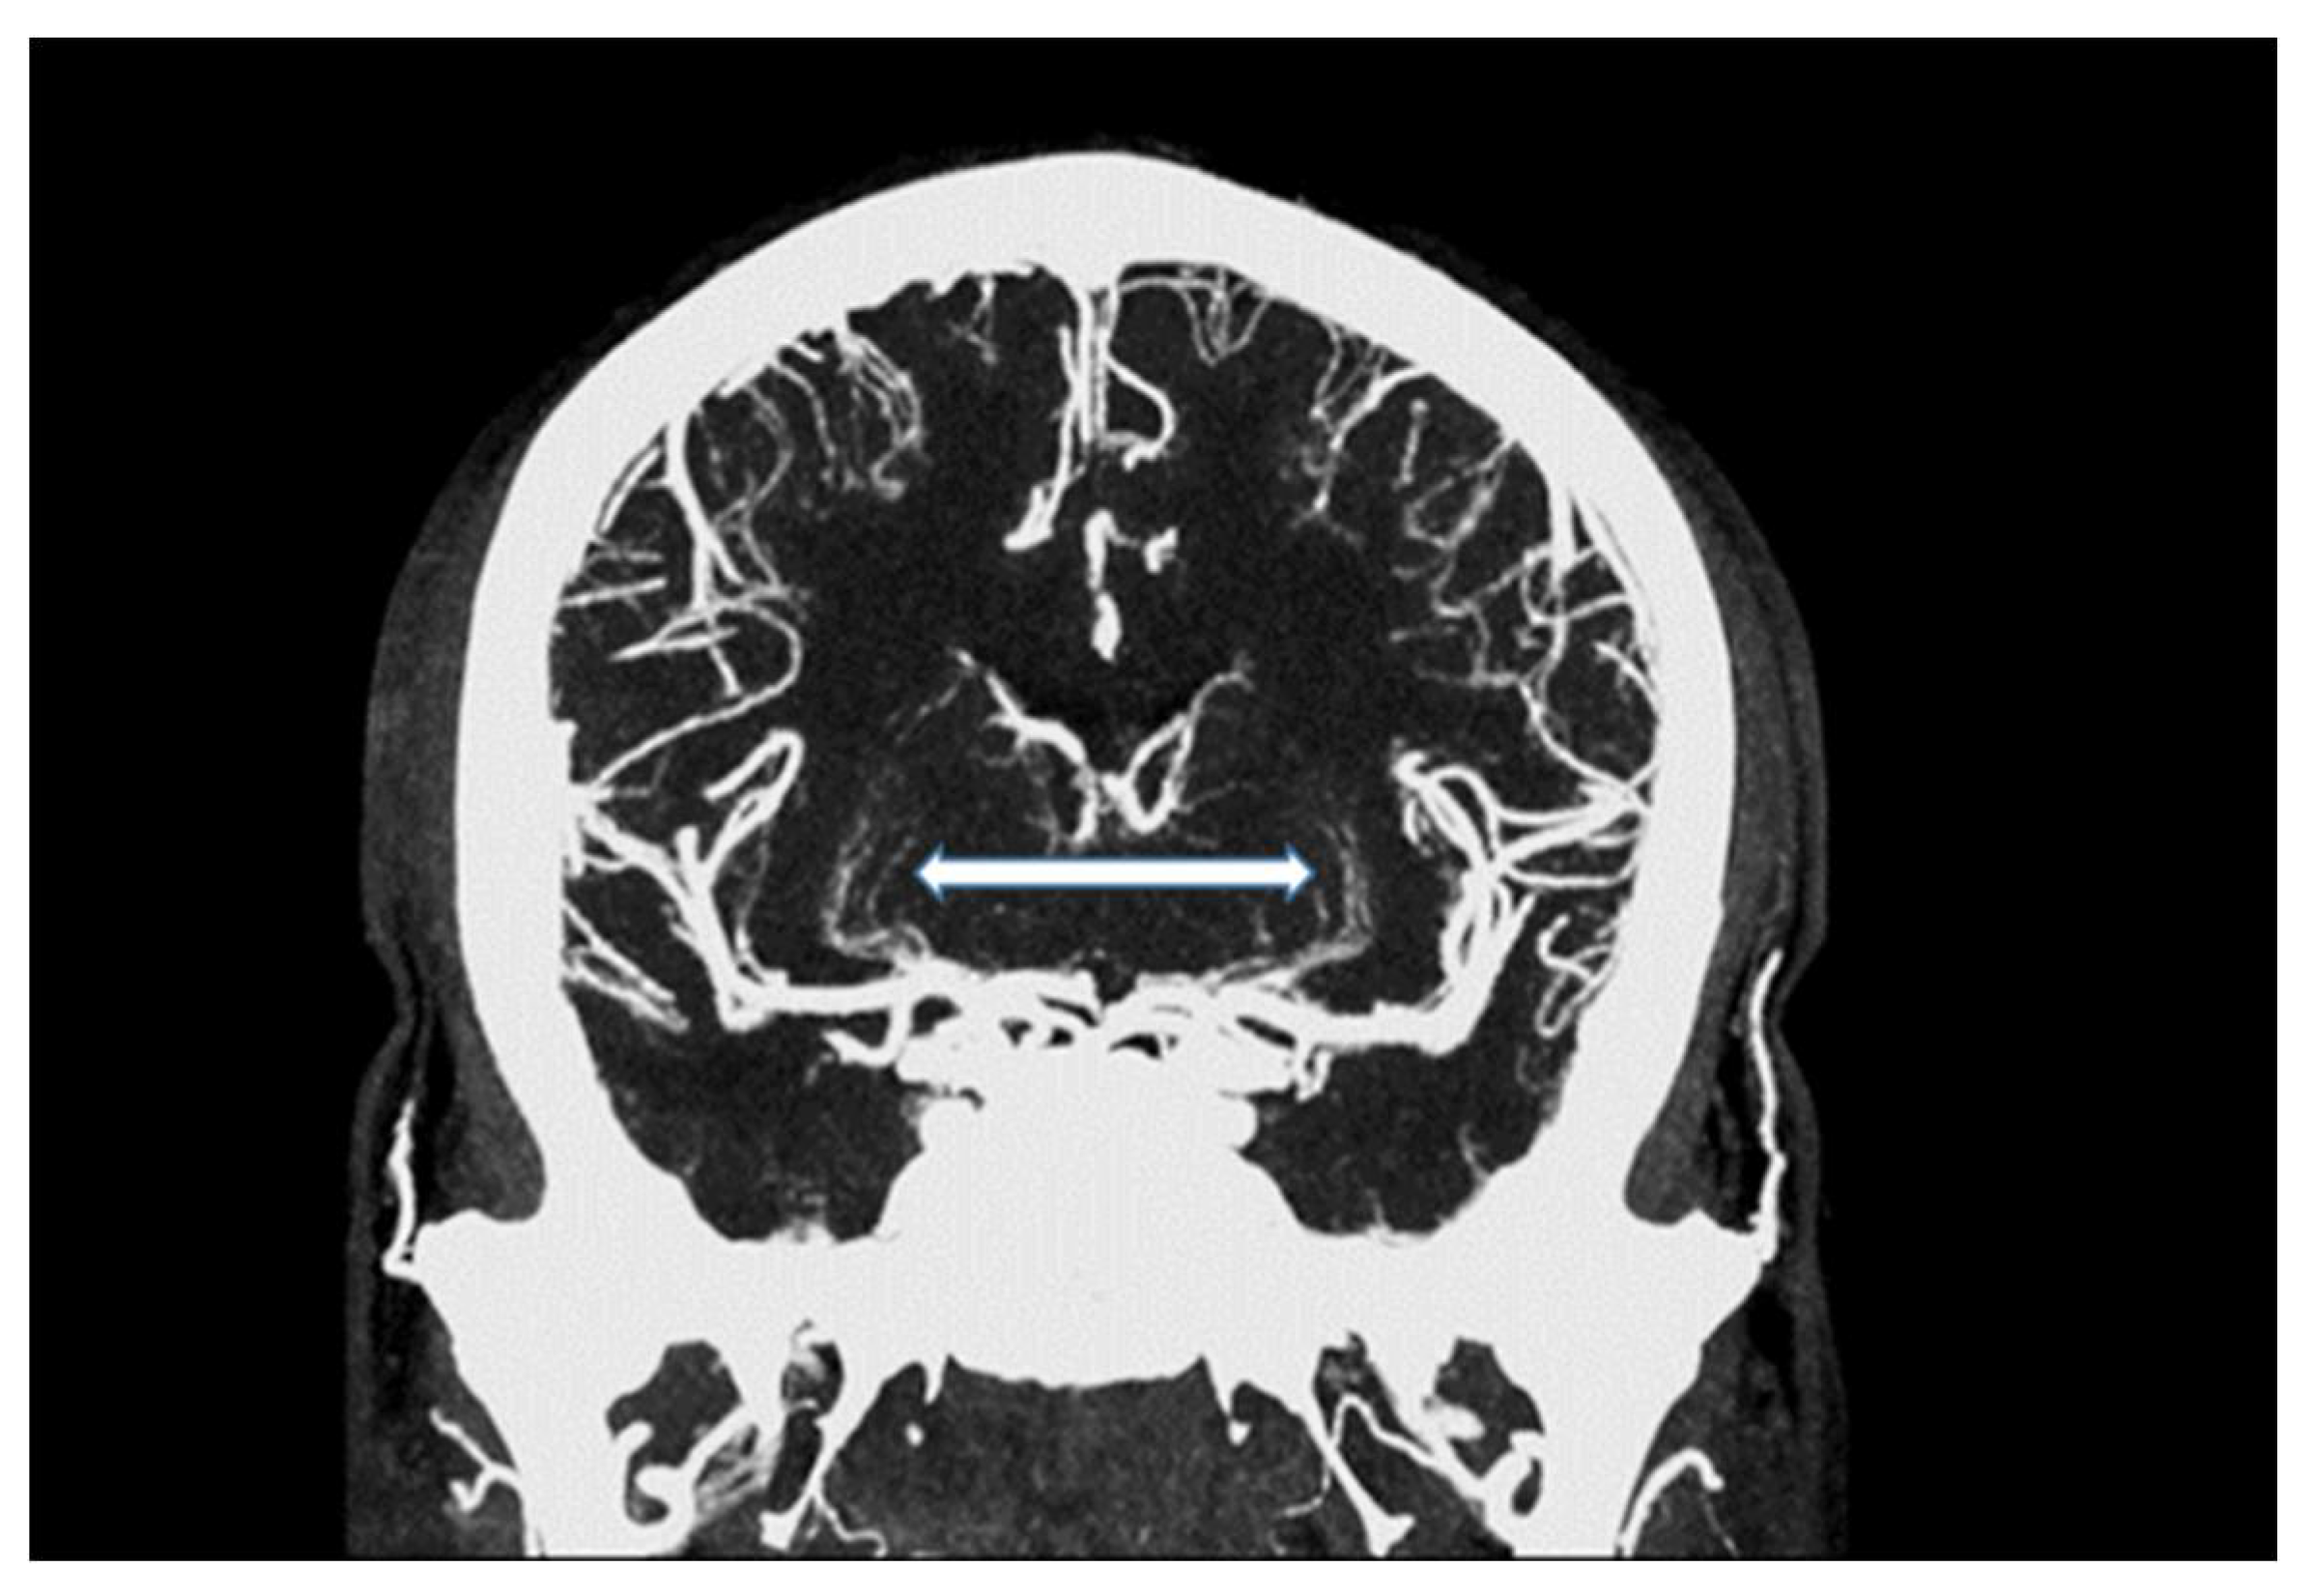

Figure 2.

Maximum intensity projection of an intracranial UHR-CTA, depicting traceability of lenticulostriate arteries (LSA; white arrow).

In summary, the subjective analysis of all images showed excellent results for the applied qualitative parameters such as overall image quality, overall contrast noise and artefacts, the latter focusing on streaks within the posterior fossa. A high-rated vessel contrast and delineation could also be observed, which were not only limited to the large cerebral vessels but also appeared in the smaller vessel sections, especially in the deep cerebral perforators (e.g., lenticulostriate arteries). Patient examples are given in Figure 2, Figure 3, Figure 4 and Figure 5. Interrater reliability was ascertained by applying Cohen’s kappa coefficient and showed a fair agreement (k = 0.26).

We were able to show that excellent image qualities were generated even though radiation exposure could be kept at explicitly moderate levels [10]. In addition, the occurrence of Hounsfield artefacts that frequently hinder the assessment of the vertebrobasilar system and the brainstem were also considerably low, enabling an advanced image interpretability. Both quantitative and qualitative evaluation of the UHR-CTAs confirmed our hypothesis of a highly remarkable improvement in image quality and spatial resolution. In particular, a high vascular contrast and a distinctly defined demarcation of the extracranial as well as the intracranial vessels could be demonstrated. It is noteworthy that even the smallest perforating arteries (e.g., LSA, as shown in Figure 3) vascularizing the deep brain structures become diagnostically accessible by UHR-CTA, which is generally not the case when using conventional CTA.